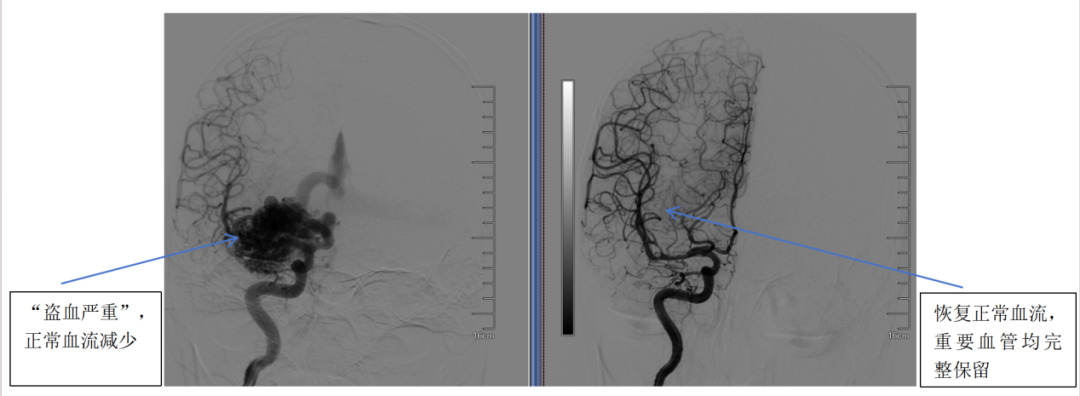

(图B:DSA全脑血管造影)

术后复查CTA显示畸形血管全部切除,复查DSA显示血流恢复正常,重要血管结构均完整保留。经康复观察,患者无任何并发症,头痛与癫痫消失,精神与记忆恢复正常。

颅内动静脉畸形(AVM)是一种先天性血管发育异常,动脉和静脉之间缺乏毛细血管网而直接相连,形成一团畸形的血管巢,它像一颗“不定时炸弹”,随时可能引发致命出血或癫痫,又像一个“小偷”,偷走原本供应正常脑组织的血液,即盗血。与大多数脑血管病好发于老年人不同,动静脉畸形好发于青壮年。

DSA全脑血管造影:比CTA更精确,且可以动态显示血流,确诊“金标准”,如图B。